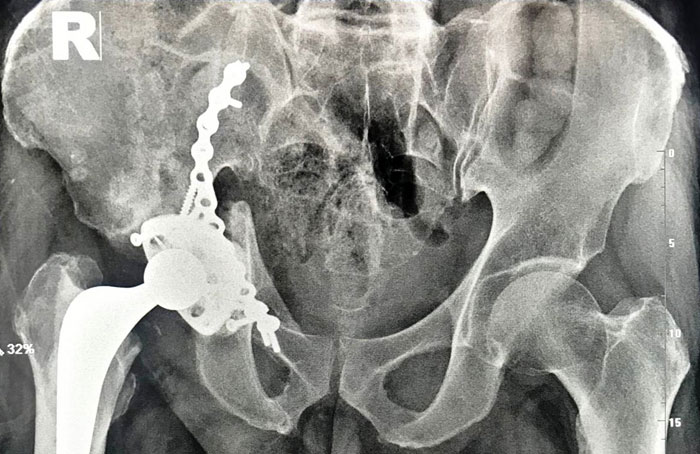

Помогли травматологам специалисты из Новосибирска, которые по заданным размерам, на основе результатов рентген- и КТ-исследований, смоделировали индивидуальный 3D-имплант. За счет средств больницы был изготовлен имплант из титанового сплава методом послойного лазерного спекания. Травматологи зафиксировали «чашу» винтами к тазу, в нее установили стандартный эндопротез.

На вторые сутки после операции пациент вертикализирован с практически полной нагрузкой на оперированную конечность; после периода реабилитации мужчина планирует вернуться к активной жизни.